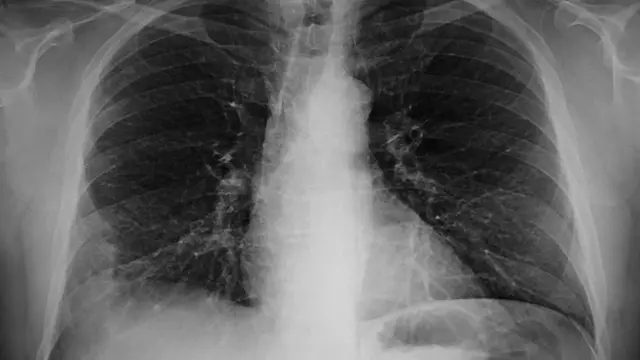

Theresa Nwachukwu, dibia bekee bụ ọkachamara n'ihe gbasara ahụike ụmụaka, kwuru na 'Pneumonia' bụ ọrịa ngụgụ.

"Ọ bụrụ na nje 'bacteria' maọbụ 'fungi' maọbụ 'virus' baa mmadụ na ngụngụ, nke a ka a na-akpọ 'Pneumonia'".

Nwachukwu kọwara na ọrịa ngụ dị icheiche n'ihi na nje na-akpata ha abụghị otu.

N'ihi nke a, etu e si agwọ ya anaghị abụcha otu ihe.

Iji maa atụ, ọ bụghị ọgwụ e ji gwọọ ọịọrịa ngụ nke nje 'bacteria' kpatara ka e ji agwọ nke 'virus'kpatara.